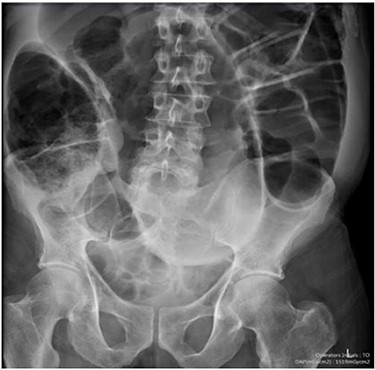

Blood tests on admission were unremarkable. Each admission, the patient’s plain abdominal films showed dilated large bowel loops consistent with sigmoid volvulus (Fig. 1). A subsequent computed tomography (CT) of the abdomen and pelvis with intravenous contrast revealed dilated large bowel and was reported as sigmoid volvulus with no evidence of perforation (Fig. 2). Caecal volvulus was not appreciated on this scan.

Case one: plain abdominal film showing dilated large bowel and the ‘coffee bean’ sign associated with sigmoid volvulus.